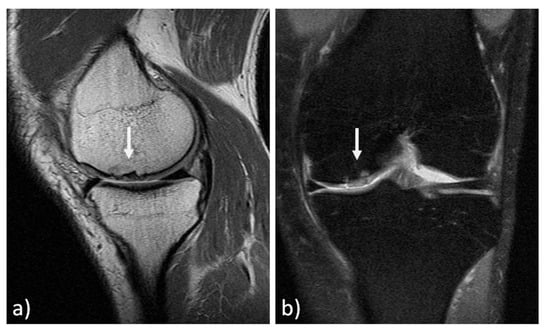

The MRI findings of 30 knees (15 mosaicplasty and 15 MACT), analyzed with the MOCART 2.0 scoring system, showed a high rate of cartilage defect filling in both groups, and a complete integration into the adjacent cartilage in half of the patients in both groups. However, the surface of the repair tissue was damaged in the majority of cases. The structure of the repair tissue was homogeneous in most cases, and the signal intensity was normal (isointense) in half of the patients in both groups. At subchondral bone level, a bony defect or bony overgrowth was reported in the majority of patients, while an edema-like marrow signal was reported in almost half of the patients in both groups (Figure 3 and Figure 4). No significant differences were reported between the two groups in the overall MOCART 2.0 scores and in all the seven subscales (Table 2).

Figure 4. MRI evaluation at 9 years’ follow-up of a medial femoral condyle lesion treated with matrix-assisted autologous chondrocyte transplantation in a 39-year-old woman. Sagittal 3D "Cube" PD (a) and coronal PD FAT SAT (b) demonstrate a good filling of the defect (arrows) and integration into adjacent cartilage, a homogeneous structure and a normal signal intensity of the repair tissue. Moreover, no significant bony defect, bony overgrowth, or major subchondral changes were detected.